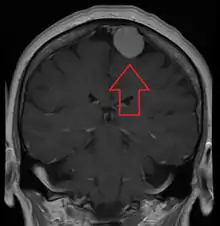

A meningioma that previously had been operated on, with surrounding edema

MRI image of a meningioma with contrast

Meningiomata are visualized readily with contrast CT, MRI with gadolinium,[20] and arteriography, all attributed to the fact that meningiomata are extra-axial and vascularized. CSF protein levels are usually found to be elevated when lumbar puncture is used to obtain spinal fluid. On T1-weighted contrast-enhanced MRI, they may show a typical dural tail sign absent in some rare forms of meningiomas.[16]